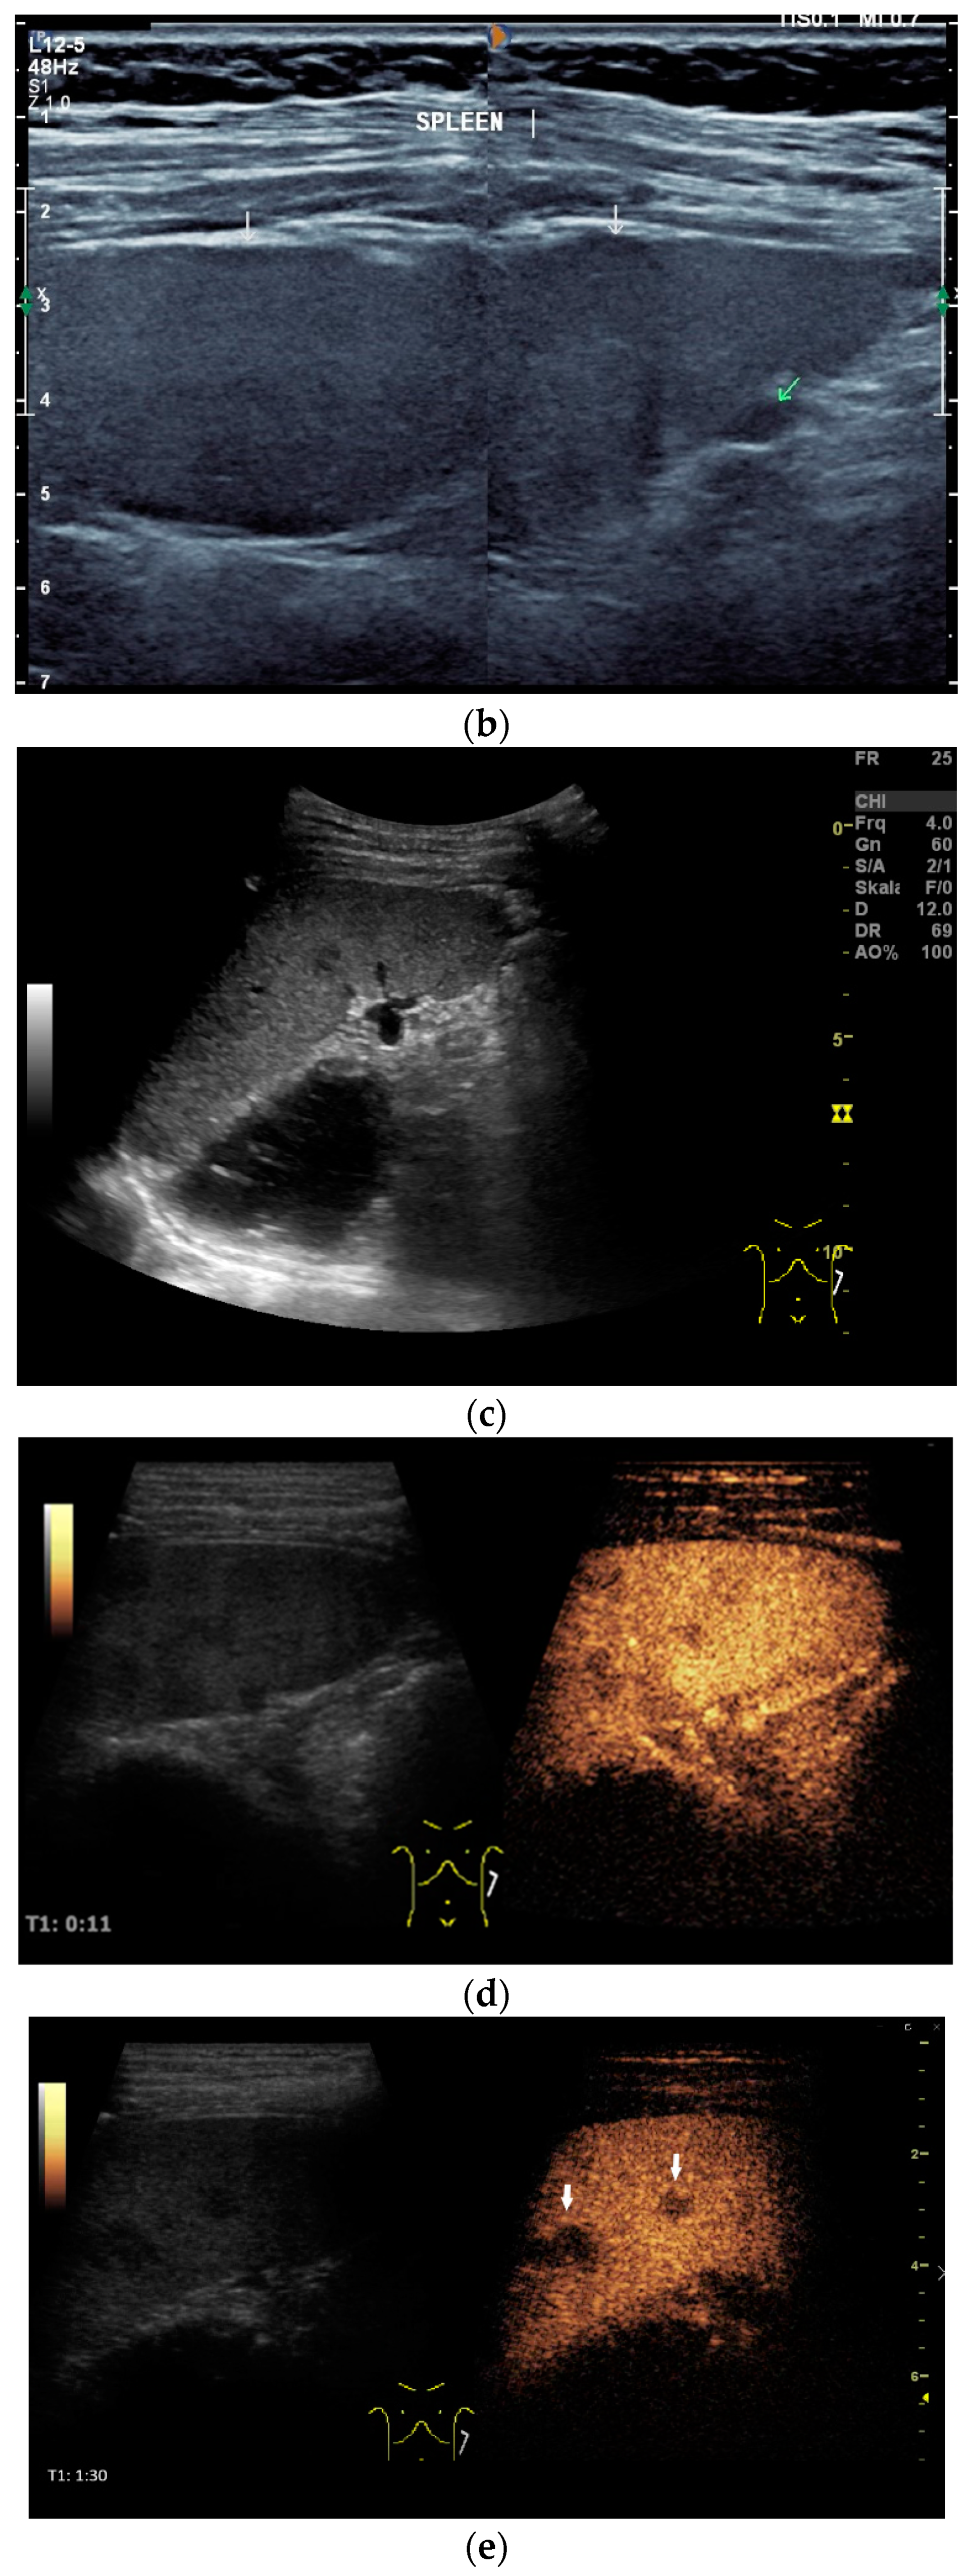

6. Liver

Liver involvement in active tuberculosis is rarely reported, with a frequency of approximately 1% [51,52]. It is more common with concomitant HIV disease at 18% [5,6,52]. Isolated tuberculosis of the liver is very rare, and has been described in just 1% of all cases [53,54]. In an autopsy study of patients with miliary pulmonary tuberculosis, 91% had liver involvement [55]. In the liver, tuberculosis manifests with diffuse- or focal-type nodular lesions. These can be micronodular (miliary) lesions or macronodular lesions [56,57,58]. A third variant is the serohepatic form, with a thickened liver capsule and subcapsular nodular lesions [56] [Figure 3a,b].

Figure 3.

Sonographic and CEUS features of hepatic tuberculosis. Subcapsular liver lesion (a); subcapsular liver lesions (white arrow) and hypoechoic lesion on the capsule (green arrow) using a linear transducer of 12 MHz (b). Caseous necrosis, histologically proven. Hypoechoic lesion with hyperechoic rim using B-mode ultrasound (right side of image). The lesion is hyperenhanced in the arterial phase at the edge of the CEUS; the center is nonenhanced with the exception of some enhanced septa (c). In the portal venous phase, the peripheral areas are hypoenhanced (d). Multiple small, smoothly bordered, non-cystic hypoechoic lesions in the liver, with no evidence of macrovessels when using Color Doppler Imaging (e). CEUS shows mild peripheral enhancement around the lesions. The lesions are without enhancement in the arterial phase (f), portal venous phase (g), and late phase (h).

The micronodular form is usually caused by hematologic seeding via the hepatic artery in disseminated disease. If the nodules are very small and cannot be delineated via ultrasound, hepatomegaly sometimes remains the only conspicuous finding from liver ultrasound, with possible manifestations in other organs.

The macronodular form is characterized by single tuberculomas or macronodular lesions. Seeding more likely often occurs from the gastrointestinal tract via the portal vein [54]. A focal or nodular form without extrahepatic tuberculosis manifestation is very rare [59].

Abscesses can develop from the caseous necrosis, but are rare [58]. The formation of a multiseptated liver abscess with numerous septa has also been described in a case study [60] [Figure 3c–g].

The morphological correlate of hepatic tuberculosis is granulomatous inflammation, characterized by central caseous necrosis with peripheral granulation tissue. Both melting abscesses and calcified nodules may occur in the course of the disease.

Ultrasound presents hypoechoic or isoechoic liver lesions [56]. Hyperechoic lesions are rarely described (although, these can be found in hepatitis B infections and hepatitis C-related liver cirrhosis; however, histologically confirmed cases have categorized these as tuberculoma related, and not as regenerative nodule or hepatocellular carcinoma (HCC)) [59,61]. Depending on the stage of the disease, the inflammatory lesions are homogeneously hyperenhanced via CEUS. Most lesions develop a washout in the portal venous phase. Melting abscesses show a hyperenhanced rim with either a hypoenhanced or nonenhanced center or a heterogeneous enhancement [62,63] [Figure 3c,d]. Vascular complications, such as portal vein thrombosis, have been caustically described and found to be in connection with hepatitis B [54,64].